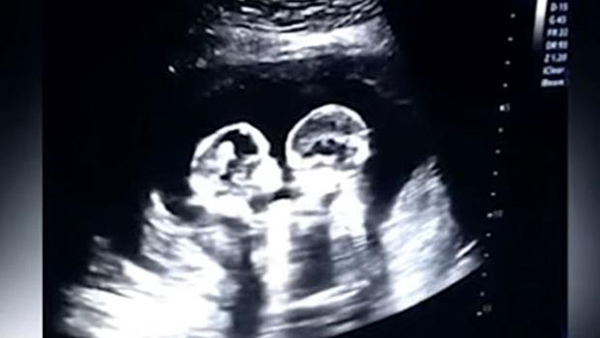

Una ecografía muestra a dos gemelas peleándose en el vientre de su madre

Beijing,18/04/2019(El Pueblo en Línea) - La sorpresa que se llevó una embarazada en China cuando fue a hacerse una ecografía se ha hecho viral en todo el mundo. El vídeo, difundido en YouTube, muestra cómo las gemelas de las que está embarazada se pelean dentro de su vientre. Unas imágenes que no han dejado indiferentes a los usuarios, que ya han especulado sobre la picardía de las ni?as cuando nazcan, según ABC.

Fue el padre de las ni?as, Tao, quien grabó el vídeo durante una de las ecografías, llevada a cabo a finales del a?o pasado. Al hombre, de 28 a?os, le pareció gracioso grabar cómo sus hijas se peleaban, algo habitual en hermanos, pero en este caso aún dentro del vientre de la madre. Sin embargo, nunca pensó que se convertirían ?en estrellas de internet antes de nacer?, dijo a ?The Paper?.

Desde que se subió a YouTube, el vídeo no ha dejado de acumular reproducciones y ?me gusta?. Pero también hubo quien fue más allá y analizó que las gemelas compartían el mismo saco amniótico, lo que puede suponer un embarazo de riesgo.

Pero todo fue bien, y las gemelas nacieron sanas el pasado 8 de abril por cesárea.